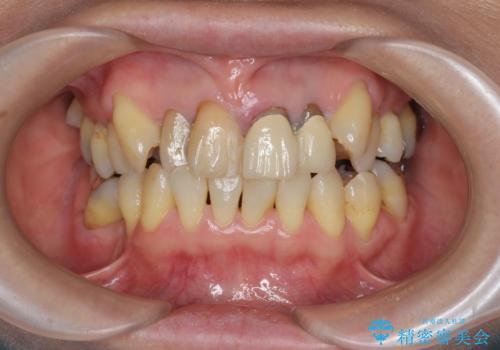

- 前歯のぐらつき、見た目の改善を希望され来院されました。

ぐらつきのある歯は、破折が認められ、その他前歯も不十分な根管治療や不適合なクラウン、レジン修復により審美障害が起きています。

問題を一つづつ丁寧に解決し、前歯の審美性の改善を計画します。